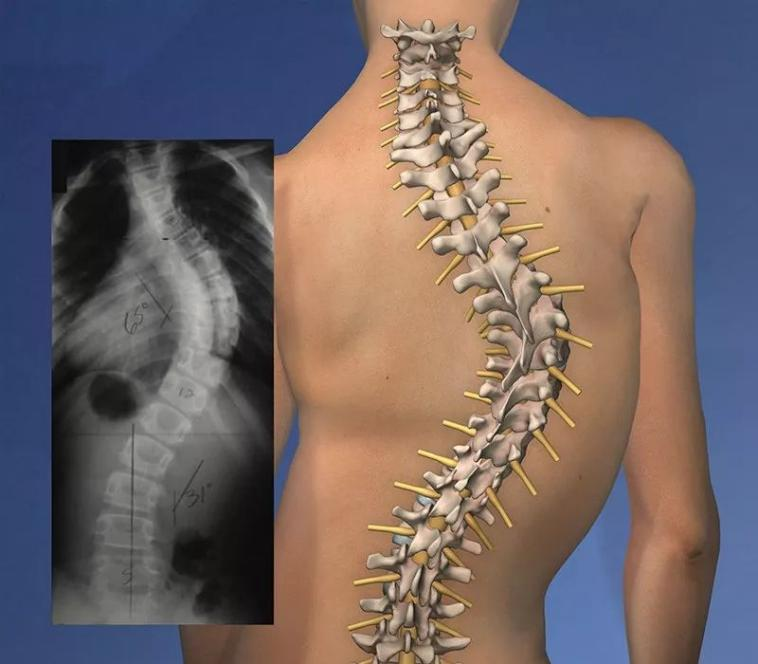

通俗来讲,就是脊柱“长歪了”,处于三维畸形状态。国际脊柱侧弯研究学会对脊柱侧弯定义为:如果Cobb角大于10度则定义为脊柱侧弯。

家长自查出孩子有脊柱侧弯,未及时干预,导致侧弯进一步加重。

图片

四、脊柱侧弯需要做手术吗?

脊柱侧弯根据侧弯程度可以分为轻、中、重度。Cobb 角<10°时,不需特殊处理,定期随访观察即可;若是轻中度的青少年主要采用保守治疗,包括手法、康复运动训练、佩戴支具等。

1.轻度:Cobb 角在10°~25°时,建议康复治疗。

2.中度:Cobb角25°~45°时,建议康复治疗+支具

3.重度:Cobb 角≥45°时,建议实施手术治疗+术后康复。